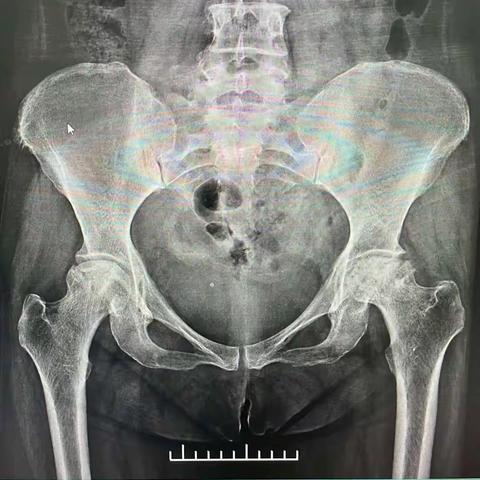

一例肥胖患者双髋关节置换术在骨一科成功实施